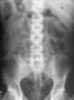

Abnormal right upper quadrant abdominal gas collection